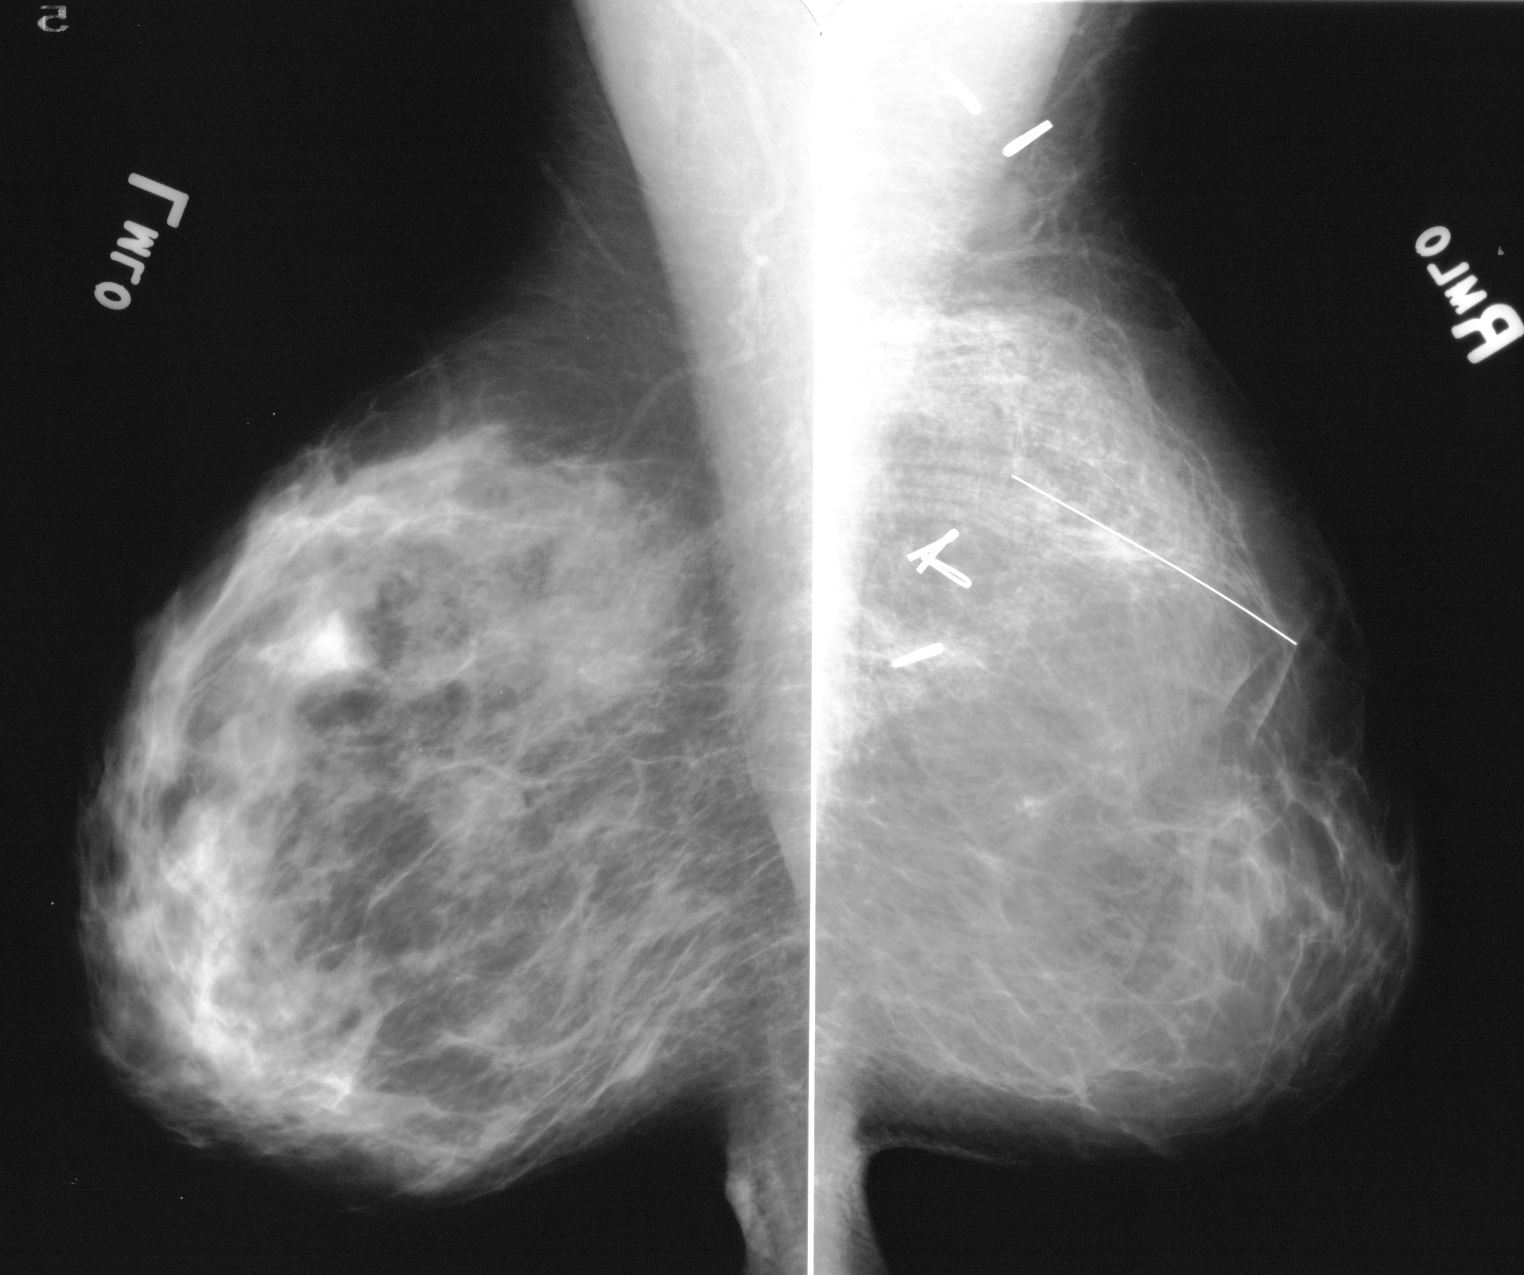

◂Breast Anatomy